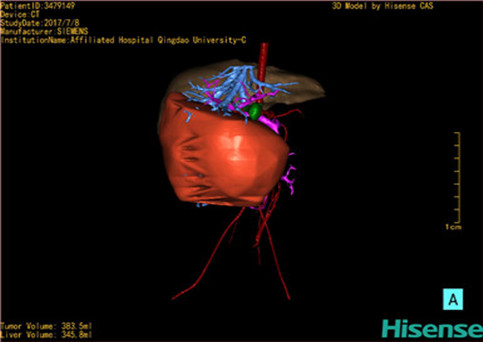

近年来由于数字医学的发展,基于可视化三维重建技术的计算机辅助手术系统极大推进了小儿肝脏肿瘤的精准手术的进步。可以立体透视肝脏解剖、精确掌握肝段的边界、精确测算肝段乃至任意血管所支配的功能体积、准确定位病灶及其与邻近血管的解剖关系,最终对不同手术方案进行比较、筛选和优化。因此,计算机辅助手术规划系统是实现精准肝切除的有力辅助工具,是未来数字外科、精准外科等21世纪外科新理念的重要技术支撑。

计算机辅助手术规划系统具有良好的操作可行性、计算准确性和三维显示效果,可半透明、交互式显示真实的肝内立体解剖关系和空间管道变异,准确计算肝内管道的直径、走行角度,两点间的垂直距离,和任意血管的支配或引流范围等传统二维影像无法获取的信息,有助于实施个体化手术,提高了手术的确定性、预见性和可控性。计算机辅助手术规划系统可直观显示预留肝脏的结构和功能,并可通过虚拟切割功能辅助术者对手术方案进行蹄选和优化,系统评估手术风险和制定对策,改变了部分二维规划的术式和切除范围,使部分二维规划认为不能切除的患者成功手术,提高了手术的根治性、安全性和病变的可切除性,更加符合精准肝脏外科的术前规划要求。详见第11章。

随着计算机技术及影像检查技术的不断发展,以精确的术前影像学和功能评估、精细的手术操作为核心的精准肝切除技术日益受到重视。基于数字医学的计算机辅助手术技术(computer-assisted surgery,CAS)则是实现肝脏精准手术操作的基础。计算机辅助手术系统(CAS)可将术前二维(two dimensional,2D)的CT/MRI影像数据进行三维(three dimensional,3D)重建,建立个体化的肝脏三维解剖模型,清晰显示肝脏内脉管系统的走行及解剖关系,还原病灶与其周围脉管结构的立体解剖构象,准确地对病变进行定位、定性和评估,制定合理、定量的手术方案,实施个体化的肝脏血管取舍分配方案及实施精准肝脏手术。一般认为CAS包括:创建虚拟的患者的图像;患者图像的分析与深度处理;诊断、手术前规划、手术步骤的模拟;术中实时导航。应用本技术后,由于可以更清晰地看出肿瘤的界限,特别是根据肝血管的显影,判断出肿瘤与门静脉及肝静脉的关系以在手术前较准确地估计出手术成功切除的可行性。以往部分根据普通强化CT判断无法手术的病例而被评估为可以成功切除并手术成功。